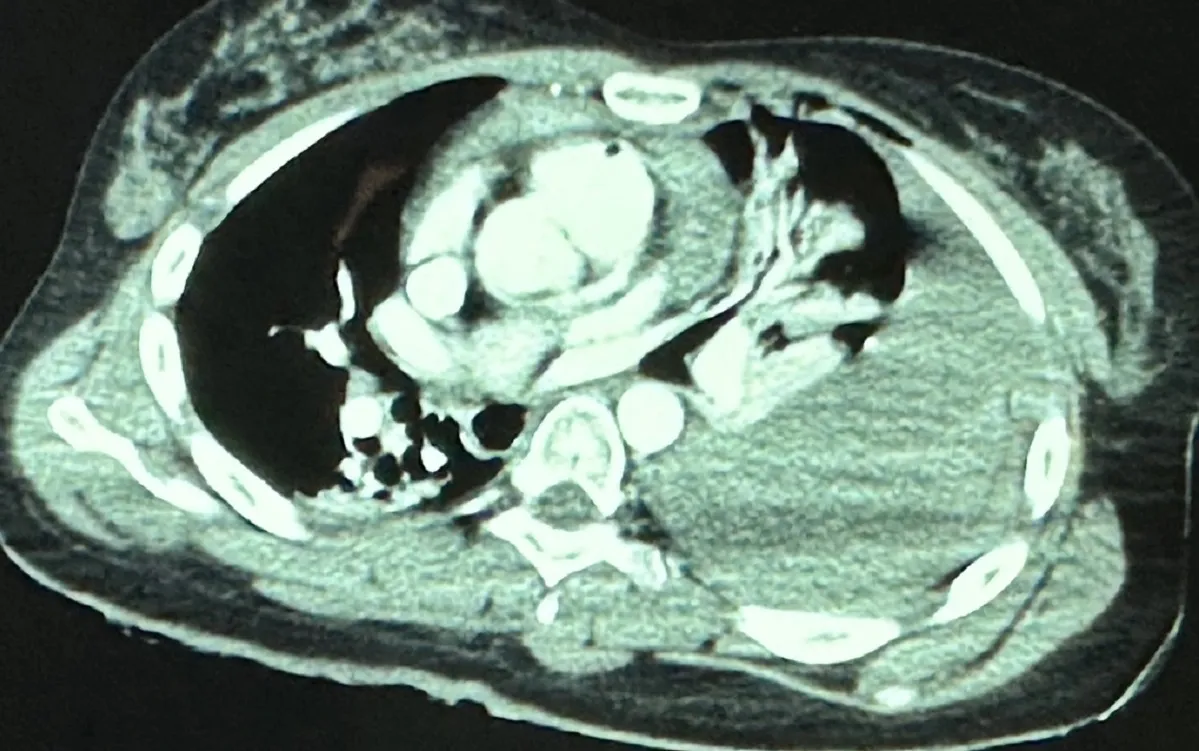

Các bác sĩ tiến hành siêu âm tim cấp cứu tại giường, thấy tràn máu màng ngoài tim lượng nhiều gây chèn ép tim, ghi nhận vết thương tim. Ngay sau đó bệnh nhân được chuyển phẫu thuật cấp cứu khẩn.

Ekip gồm các bác sĩ, điều dưỡng khoa Ngoại, khoa Phẫu thuật Gây mê hồi sức, khoa Hồi sức tích cực… đã tiến hành phẫu thuật mở ngực phát hiện màng ngoài tim căng phồng có máu bầm đen bên trong, khoang màng ngoài tim thấy máu tươi chảy ra, thấy mặt trước tâm thất phải thủng 1 lỗ dài khoảng 0.5 cm.